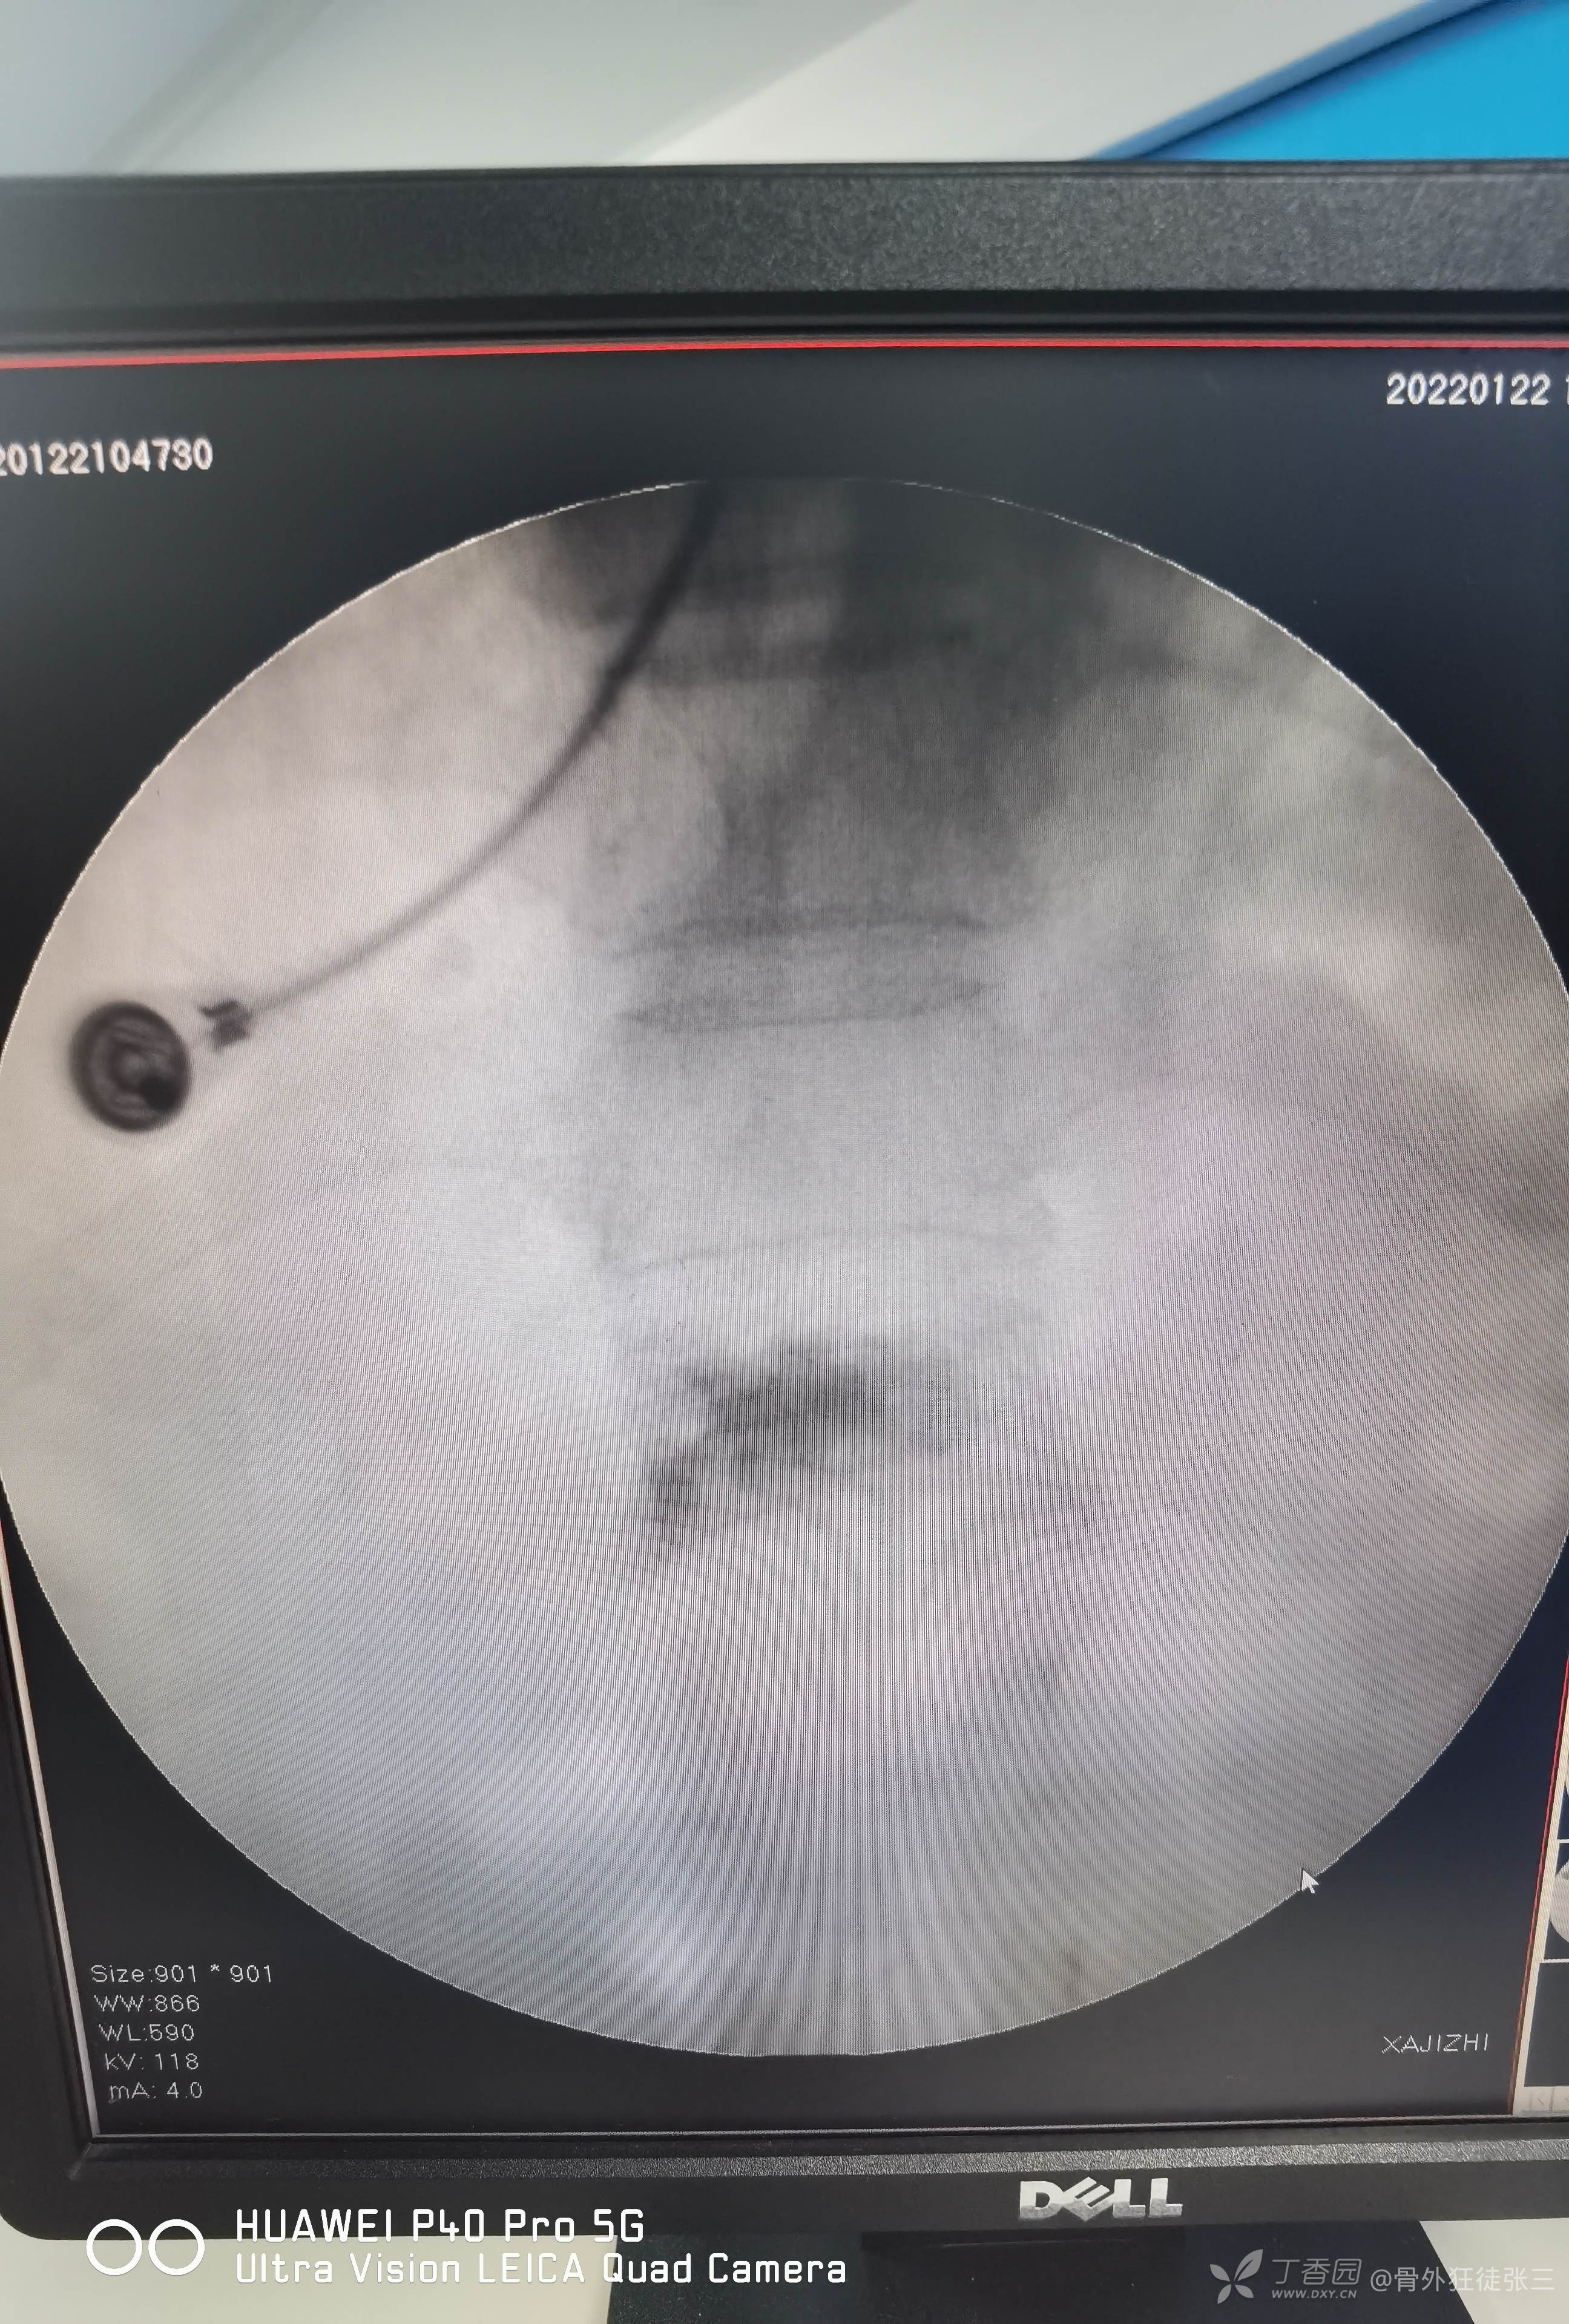

脆性骨折:胸12椎体压缩骨折椎体成形术1例

辅助检查X线,CT,核磁示:

胸12椎体压缩骨折

术前讨论后行经皮穿刺椎体成形术。

术前定位

一共注入4ml骨水泥

复查X线显示,骨水泥弥散尚可,椎体高度恢复欠佳。